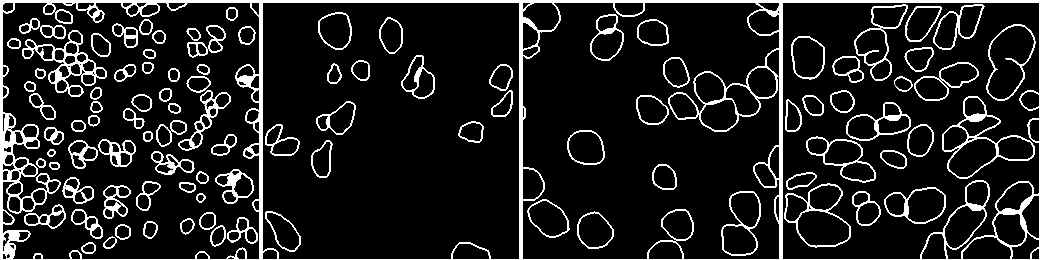

Case Study 5: Nuclei Segmentation

Nuclei segmentation is one of the basic pathology tasks in medical image analysis, whether it is traditional, [89], or deep learning-based, [90, 91, 92]. The diagnostic of pathology images is based on many terms representing objects, such as nuclei, cells, glands, and so on. Researchers extract features from these objects and use them for higher-level diagnosis. For example, tasks such as mitosis analysis, depend on nuclei segmentation and detection, because the classification of mitosis is based on the nuclei. We use a U-Net based model ([61]) to segment the nuclei on the dataset described in [50].

VI-1 Workflow

As shown in Fig. 17, the workflow includes six stages. The input loads the data from the dataset. The pre-processing converts formats and normalizes the stain of the pathology image. The dataset management splits the dataset into two sets, while the neural network uses the training set to train the model and uses the testing set to validate it.

The post-processing handles the results of the segmentation. It uses the binary normalization algorithm to improve the segmentation. The visualization tool depicts the final results to the user.

VI-4 Result and Visualization

The best result of the hyper-parameters is chosen as the final result. The DPUnet network is used as the model, and the dice function is selected as the loss function. The model is trained using 172 epochs with as the learning rate. The metric, namely AJI, reaches 0.6073, and the segmentation of the nuclei is shown in Fig. 19, while the AJI metrics of different organs are shown in Table III.

Organ | Breast | Liver | Bladder | Colon |

AJI | 0.6517 | 0.5310 | 0.6543 | 0.5424 |

Organ | Prostate | Stomach | Kidney | Mean |

AJI | 0.6147 | 0.6437 | 0.6135 | 0.6073 |